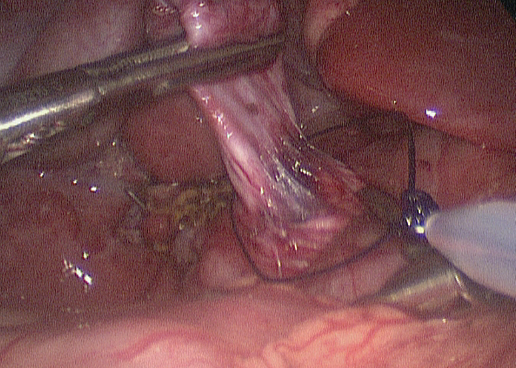

A conference among the surgical team, the liver transplantation team, and the family resulted in the decision to proceed with surgical intervention. The patient underwent laparoscopic excision of the extrahepatic choledochal cyst (Figures 3 and 4) with Roux-en-Y hepaticojejunostomy. Pathologic examination of the gallbladder revealed mild chronic cholecystitis with focal cholesterolosis, while pathologic examination of the cyst showed a mildly inflamed fibrotic wall. The patient was discharged home in stable condition.

Figure 3. A pre-tied ligature is being placed on the distal-most part of the cyst, which is being retracted superiorly. Some of the pancreas is visible at the level of the tie, which signifies the end of the dissection. The bile ducts at the liver hilum are visible just to the left of the cyst.

Figure 4. The tapered cyst is shown with the tie in place. Note that the cyst had been opened to better identify its margins during dissection of the portal vein.